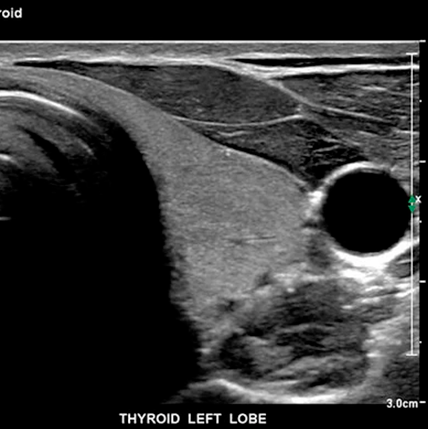

También es importante mencionar modelos orientados a ginecología y obstetricia, como el Voluson S8 de GE, ampliamente utilizado por su rendimiento en imágenes fetales en tiempo real. En cuanto a equipos portátiles, el Philips CX50, Mindray M9 y GE Logiq e han demostrado ser confiables en contextos rurales, domicilios o en pabellones quirúrgicos, donde se necesita movilidad sin perder calidad. Por otro lado, en hospitales de alta complejidad y centros de imagenología avanzada, los equipos de gama alta como el Philips EPIQ 7, Siemens Acuson Sequoia o el Canon Aplio i800 ofrecen un nivel de detalle y procesamiento de imagen que permite un diagnóstico más preciso, incluso en casos complejos.

• GE Voluson S8: Referente en gineco-obstetricia, gracias a sus funciones 4D, presets obstétricos y detección fetal en tiempo real.